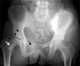

Osteopathia striata